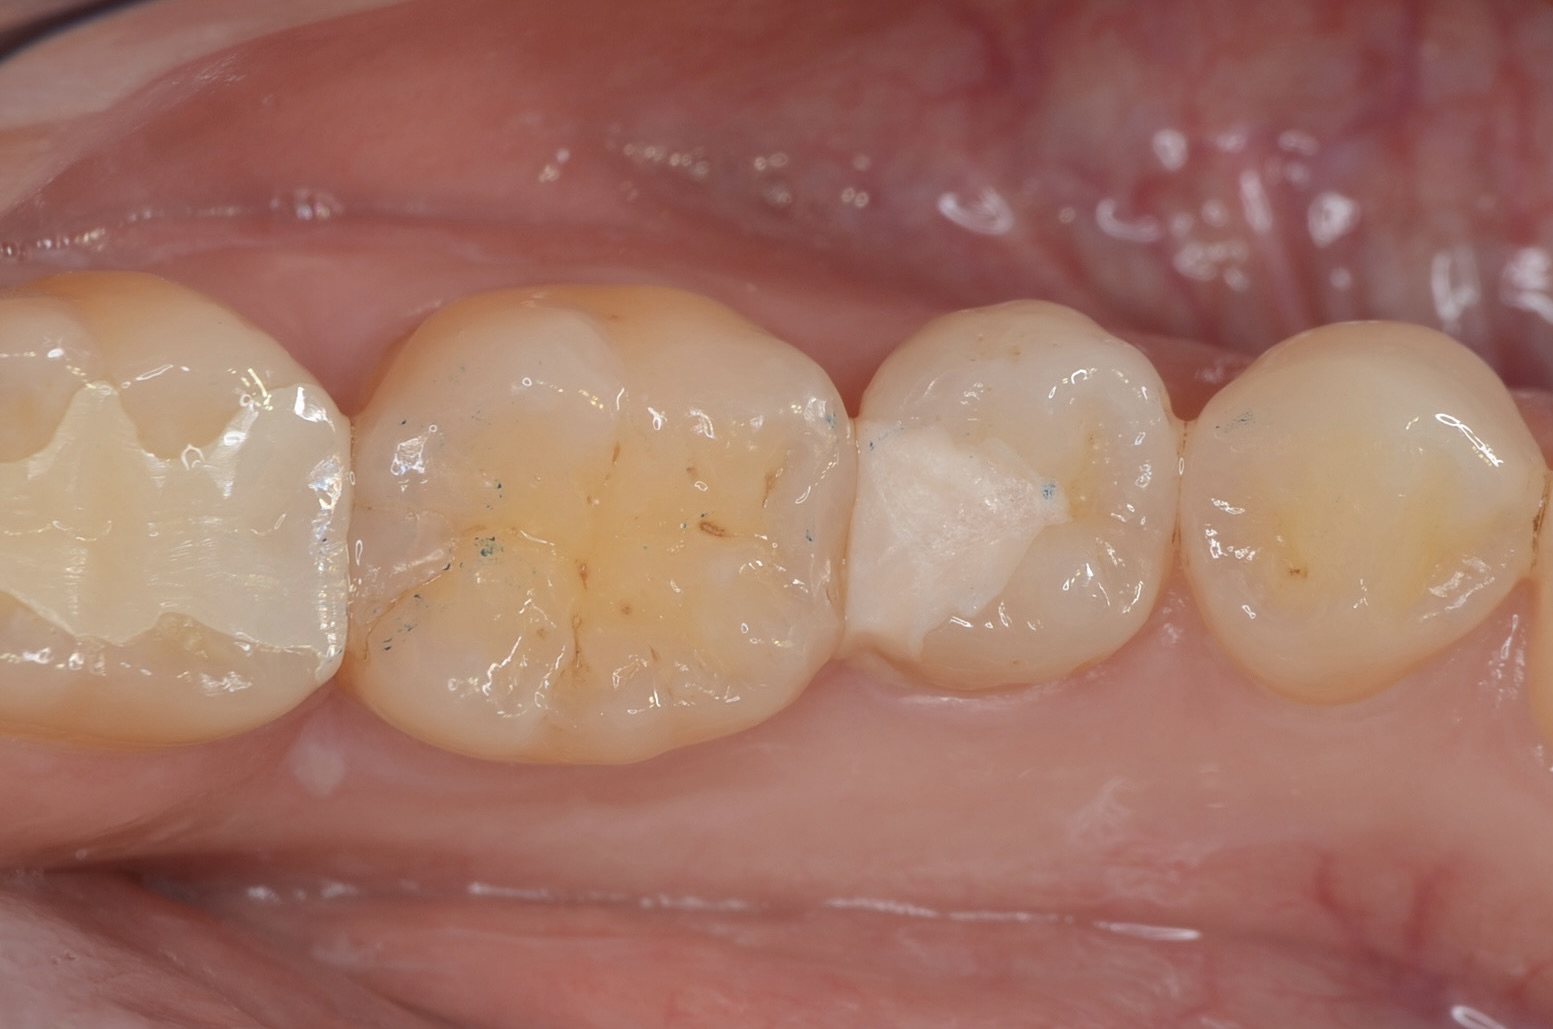

Before

After

自然な見た目に仕上がりました。噛み合わせも問題ありません。本当の審美歯科とは、見た目の美しさ・機能・清掃性が伴って成立します。 -

頬側面観